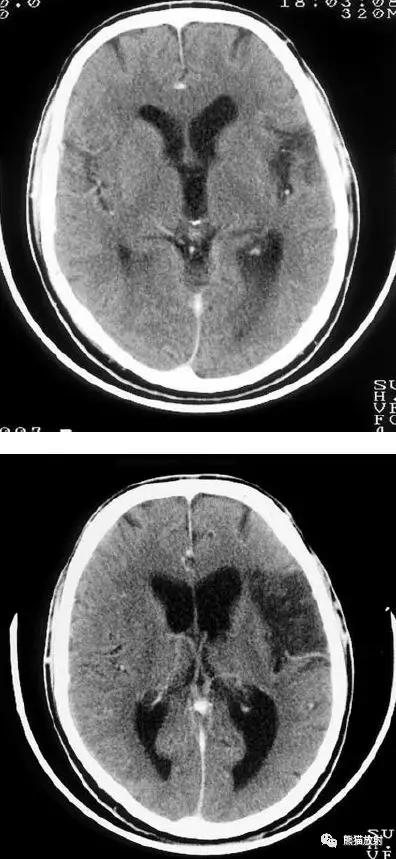

大脑中动脉区梗死:部分梗死,仅累及左侧浅表区域。

左侧大脑中动脉区完全梗死,对邻近的侧脑室产生占位效应;右侧可见其他较小的缺血性低密度区。